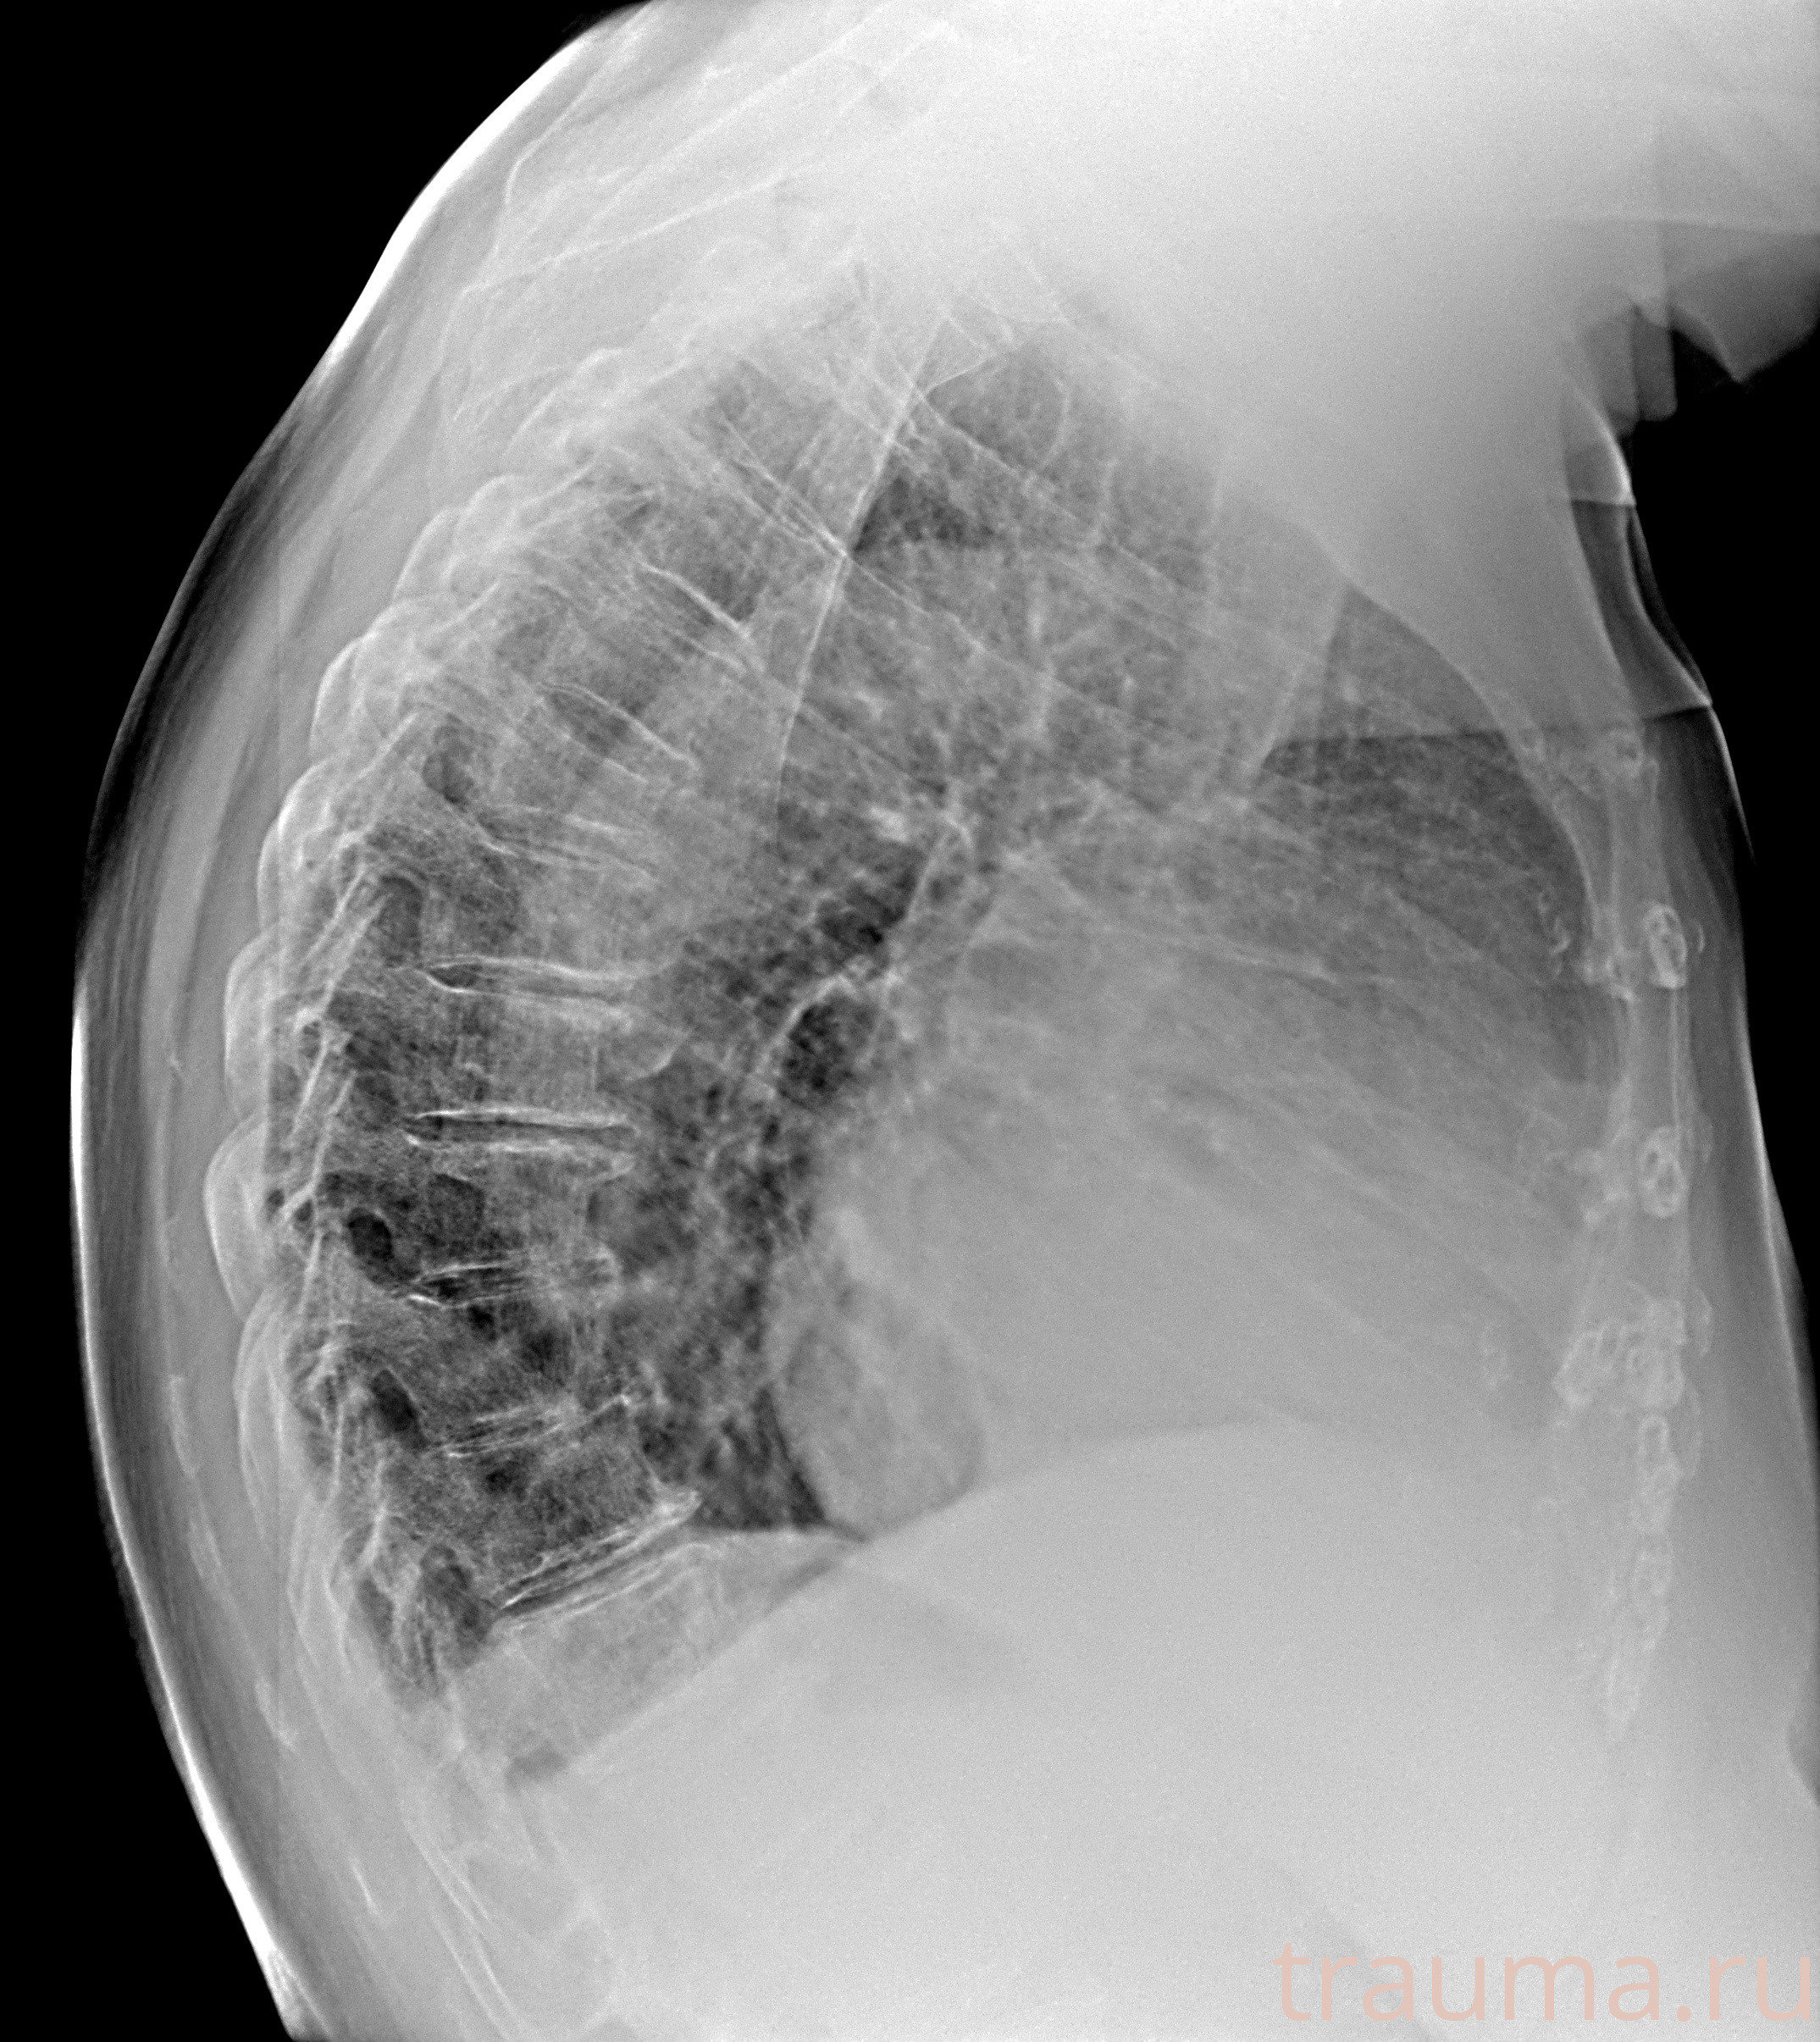

Рентгенограммы

Рентген на дому: по вашему адресу приезжает врач-рентгенолог, травматолог-ортопед с мобильным рентгеновским аппаратом, проводит диагностику травмы или заболевания, делает необходимые рентгенограммы, дает рекомендации по дальнейшему лечению. Получить качественные снимки в домашних условиях возможно благодаря уникальной методике, разработанной МосРентген Центром для института  Склифосовского